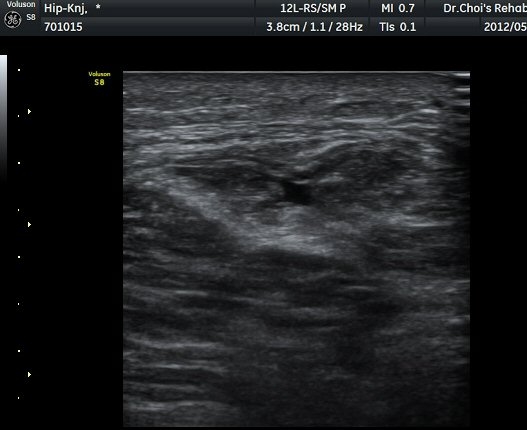

µÚÂÊ ´ëÅð ³»Ãø Ⱦ´Ü¸é°Ë»ç¿¡¼­ À̵ιڱ٠ÀåµÎ ¿ÜÃø¿¡¼­ ±ÙÀ°¼¶À¯¿Í ±Ù¸·¿¡ ÀÇÇØ Çü¼ºµÇ´Â

Á¤»óÀûÀÎ ±ÙÀ°ÀÇ ¸ð¾çÀÌ ¼Ò½ÇµÇ°í Àú¿¡ÄÚ º´º¯À¸·Î °üÂûµÈ´Ù(±×¸² 6). ŽÃËÀÚ¸¦ Á¶±Ý ¸»´ÜÀ¸·Î

À̵¿ÇÏ´Ï Àú¿¡ÄÚ º´º¯³»¿¡¼­ ±¹¼ÒÀûÀÎ ¼ö¾×Àú·ù°¡ °üÂûµÈ´Ù(±×¸² 7, 8).  À̵ιڱ٠ÀåµÎ Á¾´Ü¸é